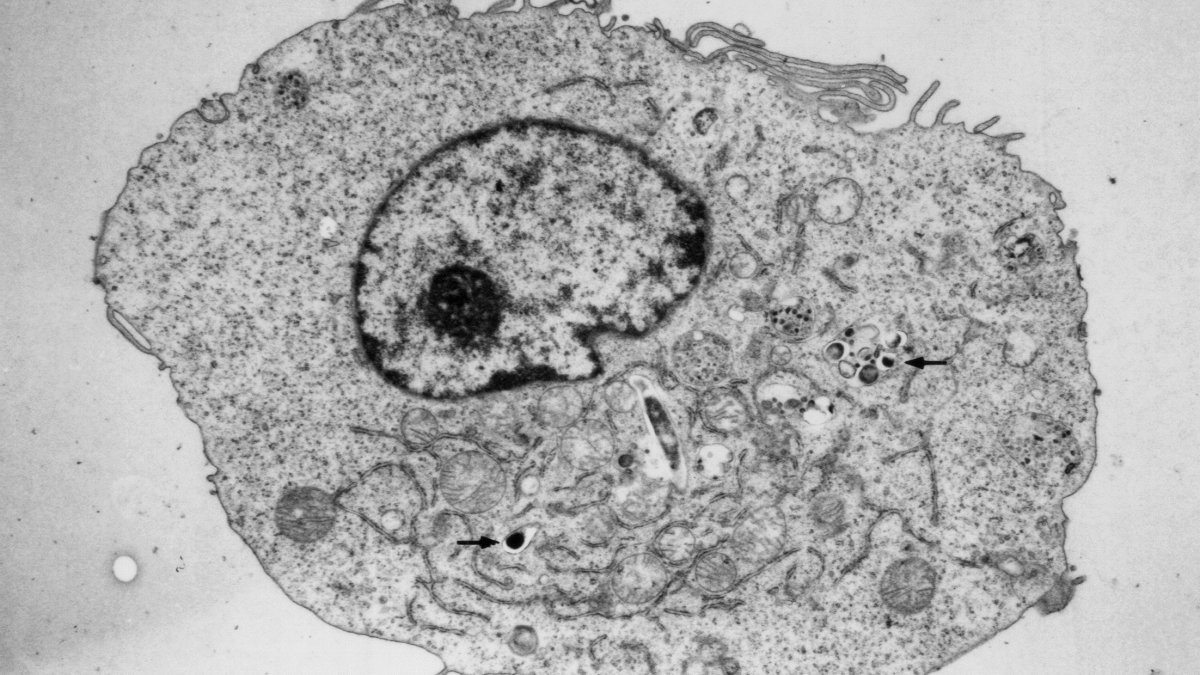

An electron micrograph of an M. tuberculosis infected macrophage. Arrows show the intracellular pathogen residing within this toxic environment.